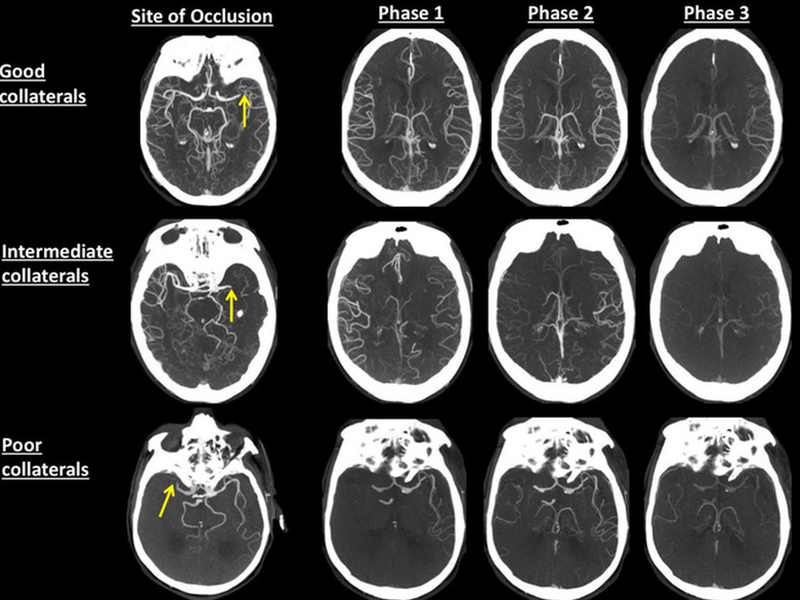

Chụp CT dựng hình mạch máu não là một trong những phương pháp tối ưu nhằm phát hiện kịp thời các tổn thương xuất huyết não và nhồi máu não. Ngoài ra, kỹ thuật này còn giúp bác sĩ lượng hóa tổn thương tắc mạch máu não theo vùng. Ngoài ra, chụp CT mạch máu não cũng sẽ đánh giá được các tổn thương như dị dạng động mạch não, phình động mạch não... để chẩn đoán sớm đột quỵ não.

Chụp CT mạch máu não nhằm khảo sát mạch máu trong não là kỹ thuật hình ảnh tiên tiến không xâm lấn. Bác sĩ sử dụng thuốc cản quang tiêm vào tĩnh mạch để hiển thị rõ mạch máu. Dùng một máy quét chụp lại hình ảnh của các mạch máu, sau đó tái tạo lại hình ảnh 3D bằng phần mềm trên máy tính.

Nhờ có hình ảnh 3D này mà bác sĩ chẩn đoán được chính xác cấu trúc của mạch máu trong một số bệnh như hẹp mạch trong sọ hoặc ngoài sọ, phình động mạch, (nguy cơ) đột quỵ…

Chụp CT mạch máu não: Cho hình ảnh có độ phân giải cao, rõ nét, có thể xử lý thành ảnh 3D để xác định chính xác vị trí mạch máu não bị tổn thương trong không gian.

Chụp CT mạch máu não là một trong những phương pháp tối ưu nhằm phát hiện kịp thời các tổn thương nhồi máu não và xuất huyết não, giúp lượng hóa tổn thương tắc mạch máu não theo vùng, đánh giá được các tổn thương như phình động mạch não, dị dạng động mạch não... chẩn đoán sớm đột quỵ não.